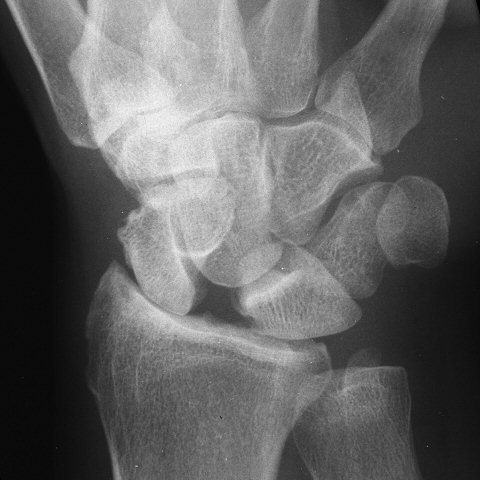

Proximal Row Carpectomy

Proximal row carpectomy for painful scapholunate dissociation with radioscaphoid arthritis. These are steps taken from the video at the bottom of this page.